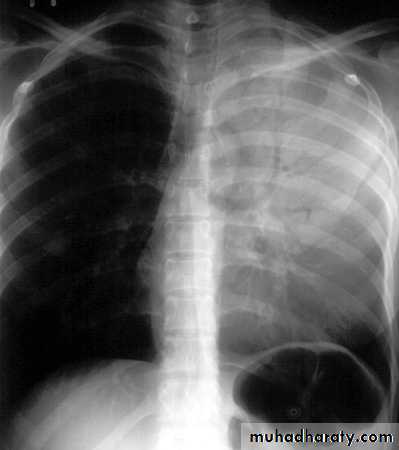

Tension pneumothorax.

On a posteroanterior chest x-ray (A), the left hemithorax is very dark or lucent because the left lung has collapsed completely (white arrows).

The tension pneumothorax can be identified because the mediastinal contents, including the heart, are shifted toward the right, and the left hemidiaphragm is flattened and depressed. A computed tomography scan done on a different patient with a tension pneumothorax (B) shows a completely collapsed right lung (arrows) and shift of the mediastinal contents to the left.

Tension Pneumothorax. Portable chest film in a 43-year-old woman with ARDS shows a large right pneumothorax with mediastinal shift and ipsilateral diaphragmatic depression, suggesting tension.

Air was evacuated under pressure during emergent placement of a right chest tube.